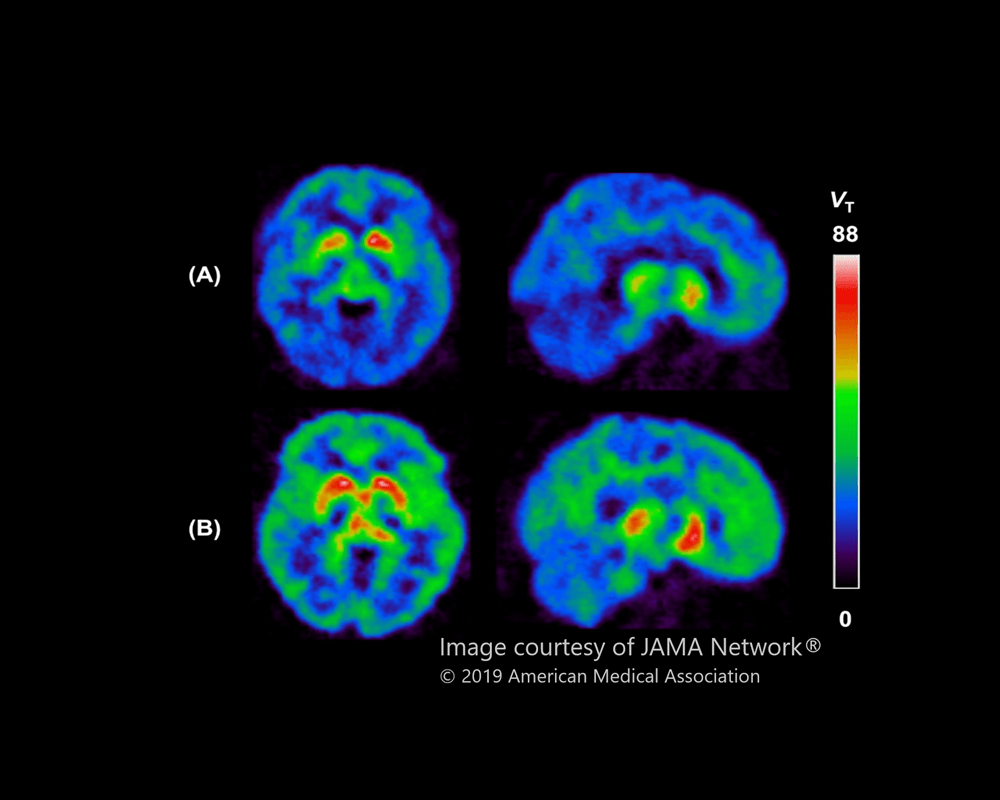

Researchers discover higher levels of a brain protein in people with clinical depression

About CAMH study reveals a new target for developing treatments for depression